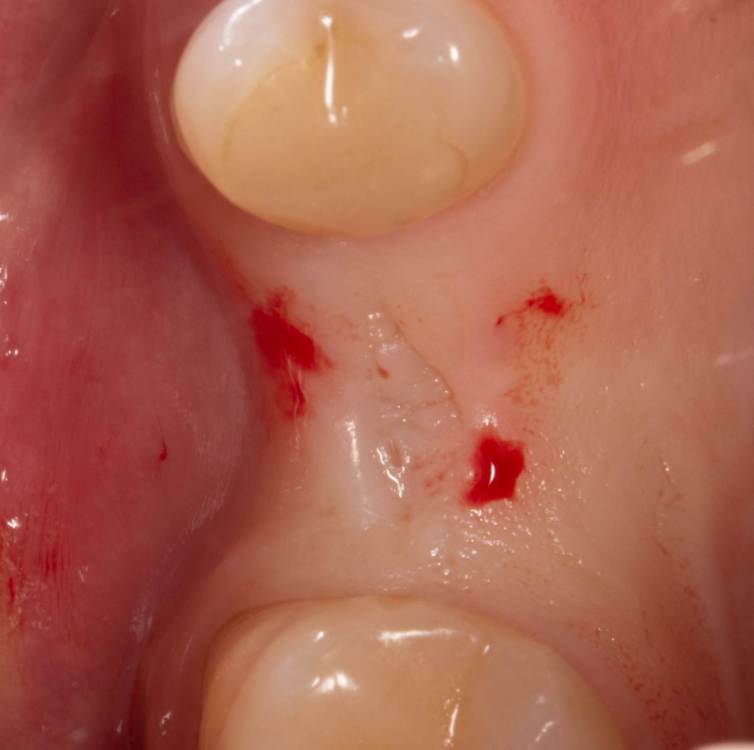

Женька Опубликовано 19 ноября, 2021 Автор Поделиться Опубликовано 19 ноября, 2021 6 дней после... все разлетелось, еще и кровотечение на 5 день открылось, думается мне из-за швов. С нёба не снял ни одного шва. Первый раз такое, что через неделю в зоне имплантации швов почти не осталось у меня... при том, что натяжения не могло возникнуть ни откуда ведь (ну ок, отёк, но зона то маленькая). В прочем, контур слизистой вроде бы получилось восстановить. Уже думаю, а не купить ли вакуум формер и каппы делать, как Настя Смолякова. Ссылка на комментарий

kriokov Опубликовано 20 ноября, 2021 Поделиться Опубликовано 20 ноября, 2021 1. кровотечение было с неба, там на фотке вроде свежий тромб видно. Пришили бы кросскрест плотно к ране на небе любой гемостатик (альвостаз, желатемп, губку) , думаю не было бы сангвиса 2. швы развалились на основной ране по причине гиперобьема за счет сст. Вы обьем вестибулярно увеличили, лоскут покрывной полнослойный толстый, отек всего этого бутерброда видимо дал раневой диастаз. Думаю не критично. Хлоргекседин пацу в помощь. ЗСЛ понравился, но показалось что кости вестибулярно маловато. Но может быть это издержки ракурса фото Ссылка на комментарий

Женька Опубликовано 10 мая, 2022 Автор Поделиться Опубликовано 10 мая, 2022 Раскрылся тут недавно. Контур естественно вогнутый был, не сработал мой сст (а если быть честным, то пожалуй умер). Снова решил попробовать ролл. Это сносный результат для этой техники? или есть "серьёзные" вопросы к её исполнению? 1 Ссылка на комментарий

Женька Опубликовано 2 июня, 2022 Автор Поделиться Опубликовано 2 июня, 2022 @annda пожалуй ролл то сработал) 4 Ссылка на комментарий